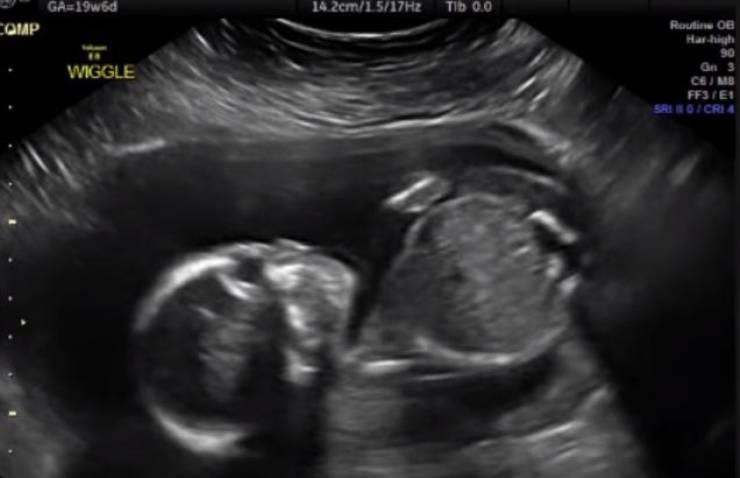

خمسة أشياء غريبة يقوم بها كل جنين في رحم أمه

لا يتذكر الناس شيئا عما فعلوه حين كانوا في أرحام أمهاتهم، لكن باحثين في الطب كشفوا عدة أمور يقوم بها أي جنين قبل قدومه إلى الحياة.